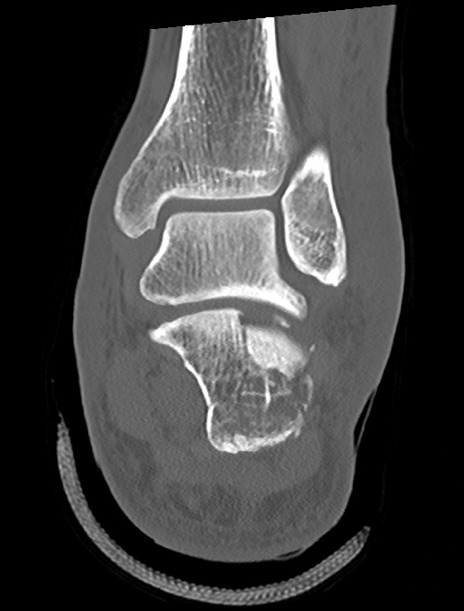

症例37 左足関節CT(冠状断像)

左足関節CT